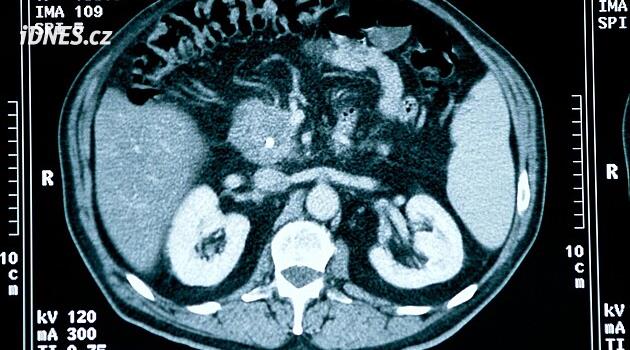

Rakovina slinivky patří mezi nejagresivnější a nejobávanější nádory. Podlehli jí například herec Patrick Swayze nebo podnikatel Steve Jobs, z českých osobností pak například Vladimír Dlouhý. Každý rok v tuzemsku lékaři odhalí 2 500 nových případů této rakoviny, přičemž až 2 300 lidí na ni umírá.